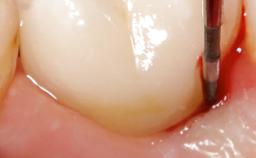

This case describes both a surgical and an anti-infective approach for the management of peri-implantitis, including treatment of the entire dentition to eliminate any deep periodontal pockets that could serve as reservoirs for bacterial re-colonization at the implant site. A 65-year-old female patient was referred to the periodontist in 2013 for assessment and management of an infection at implant 12. On examination, probing depths at implant 12 were 11 mm with suppuration and bleeding on probing.